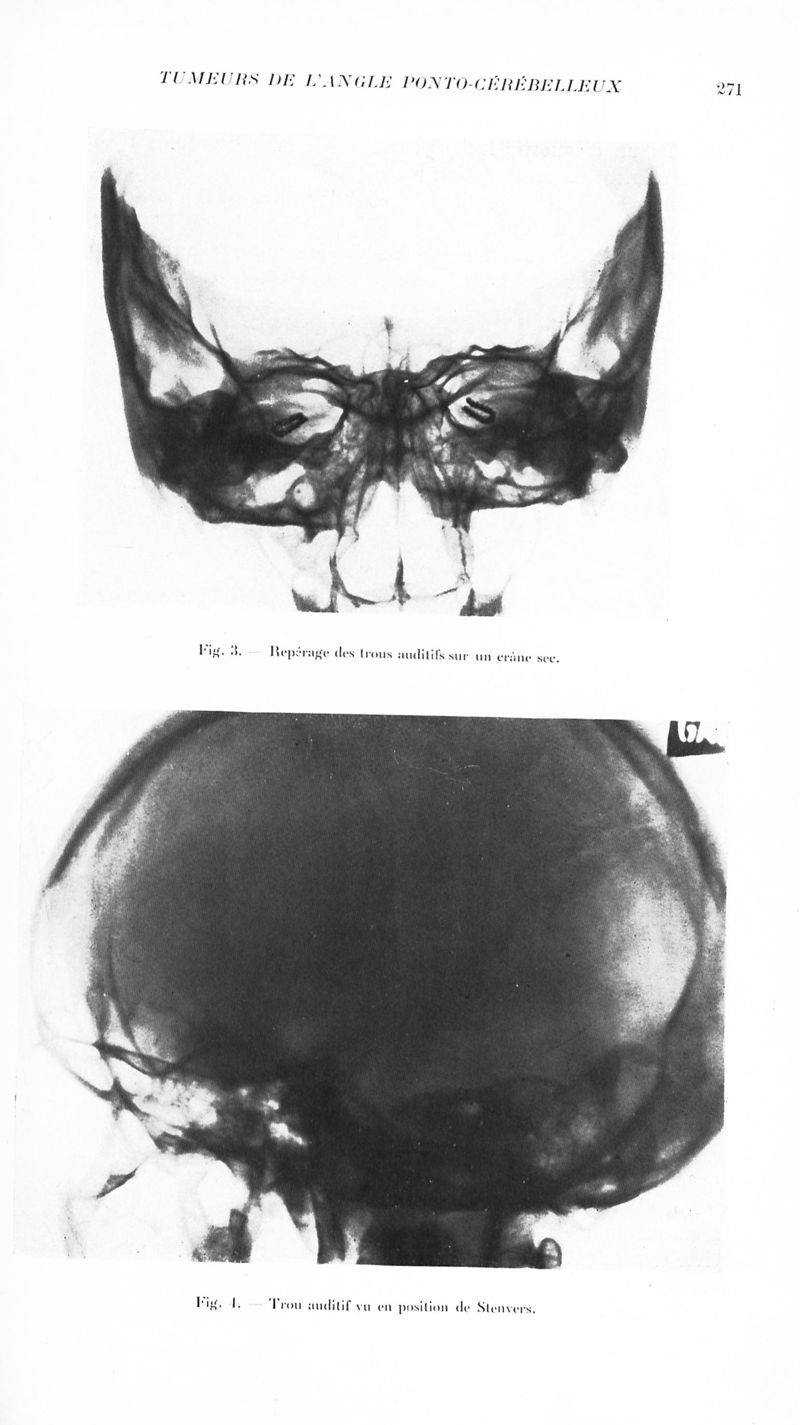

Revue neurologique

1935, vol 2. - Paris : Masson , 1935.